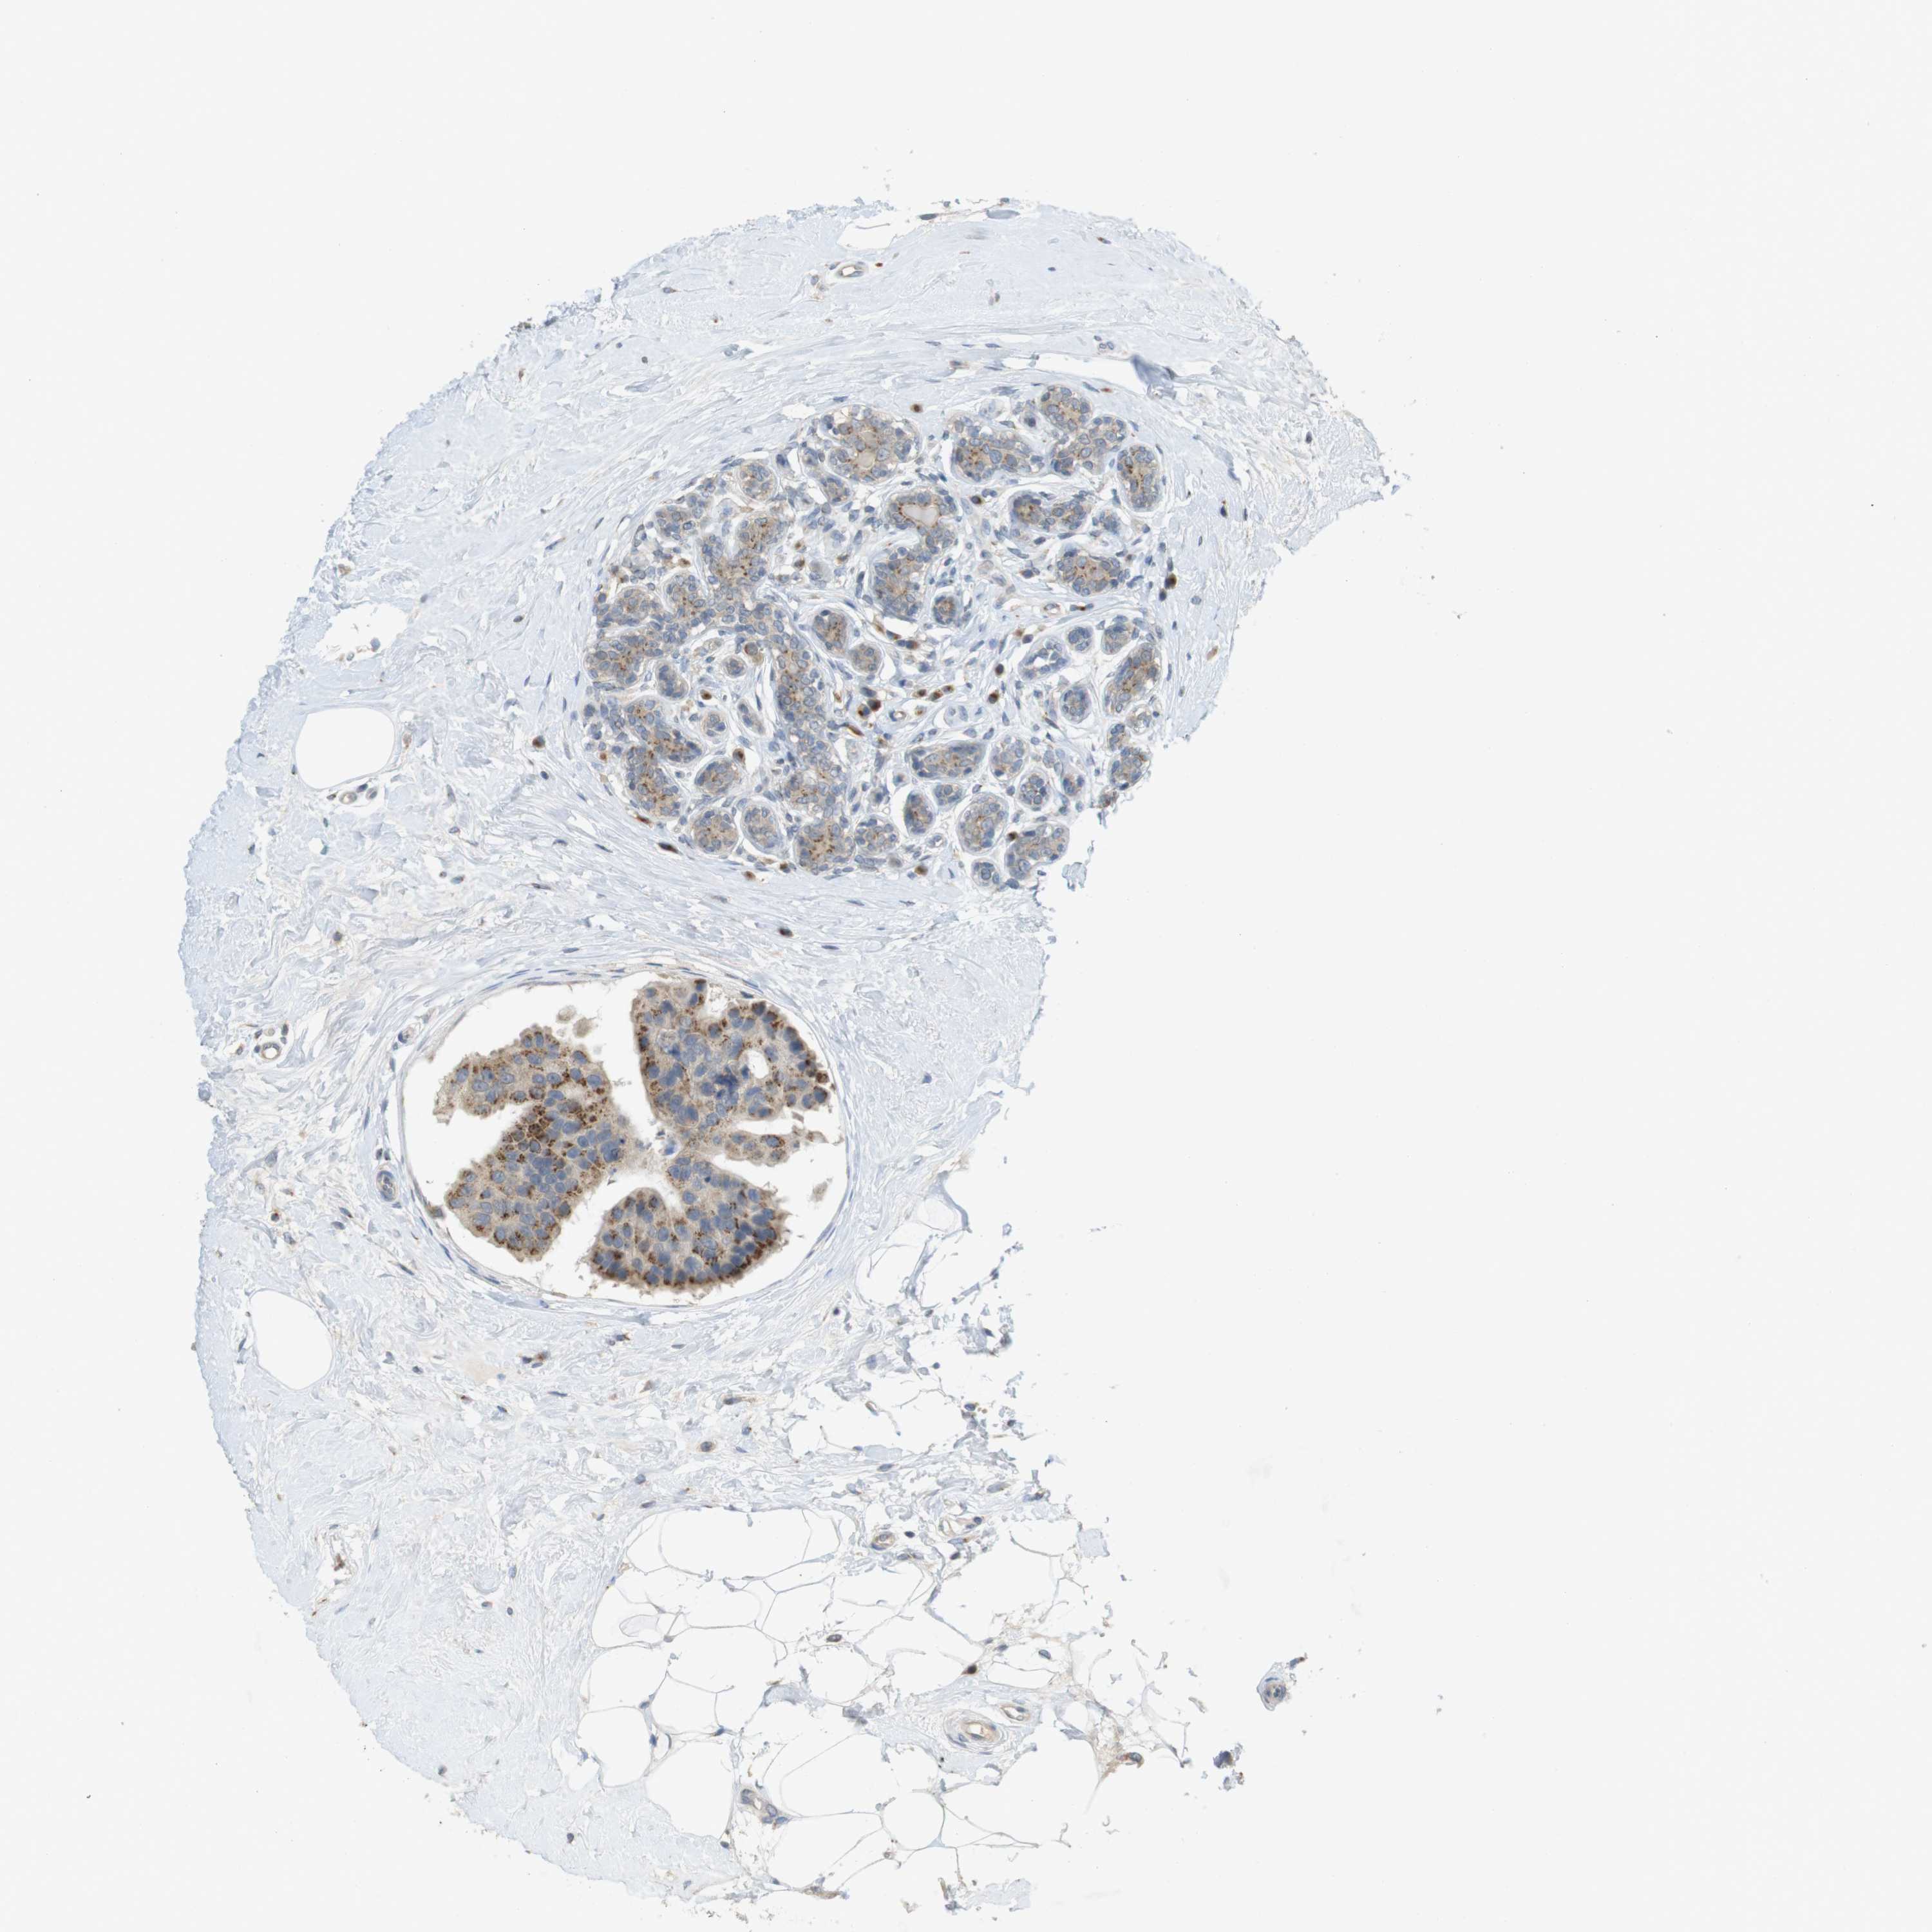

BRCA TCGA BRCA VALIDATION PROTEIN EXPRESSION